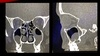

Dx

Hipertrofia de cornetes